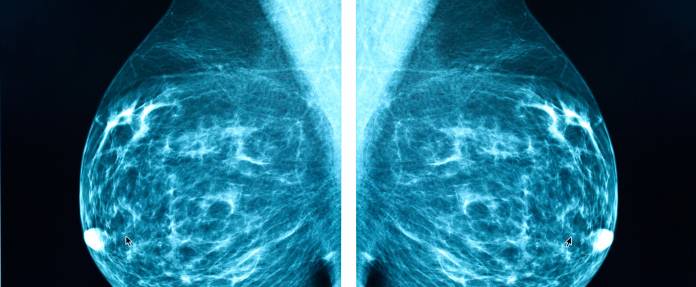

Bei der Mammographie wird eine Aufnahme mittels Röntgen gemacht. Die Röntgenstrahlen werden erzeugt und dringen durch die möglichst flach zusammengedrückte Brust zu einem Röntgenfilm auf der anderen Seite durch. Das Bild zeigt Gewebe unterschiedlicher Dichte in verschiedenen Helligkeitsgraden an, und der Untersucher kann beispielsweise Areale mit Krebsverdacht feststellen.

Bei der Mammographie wird zunächst die Brust zwischen zwei Plexiglasplatten flachgedrückt. Dann erfolgt die Aufnahme mittels eines Röntgengeräts, wobei jede Brust aus zwei verschiedenen Richtungen untersucht wird. Der Arzt beurteilt die Aufnahmen und sucht nach Auffälligkeiten, die z. B. auf Brustkrebs hindeuten können.